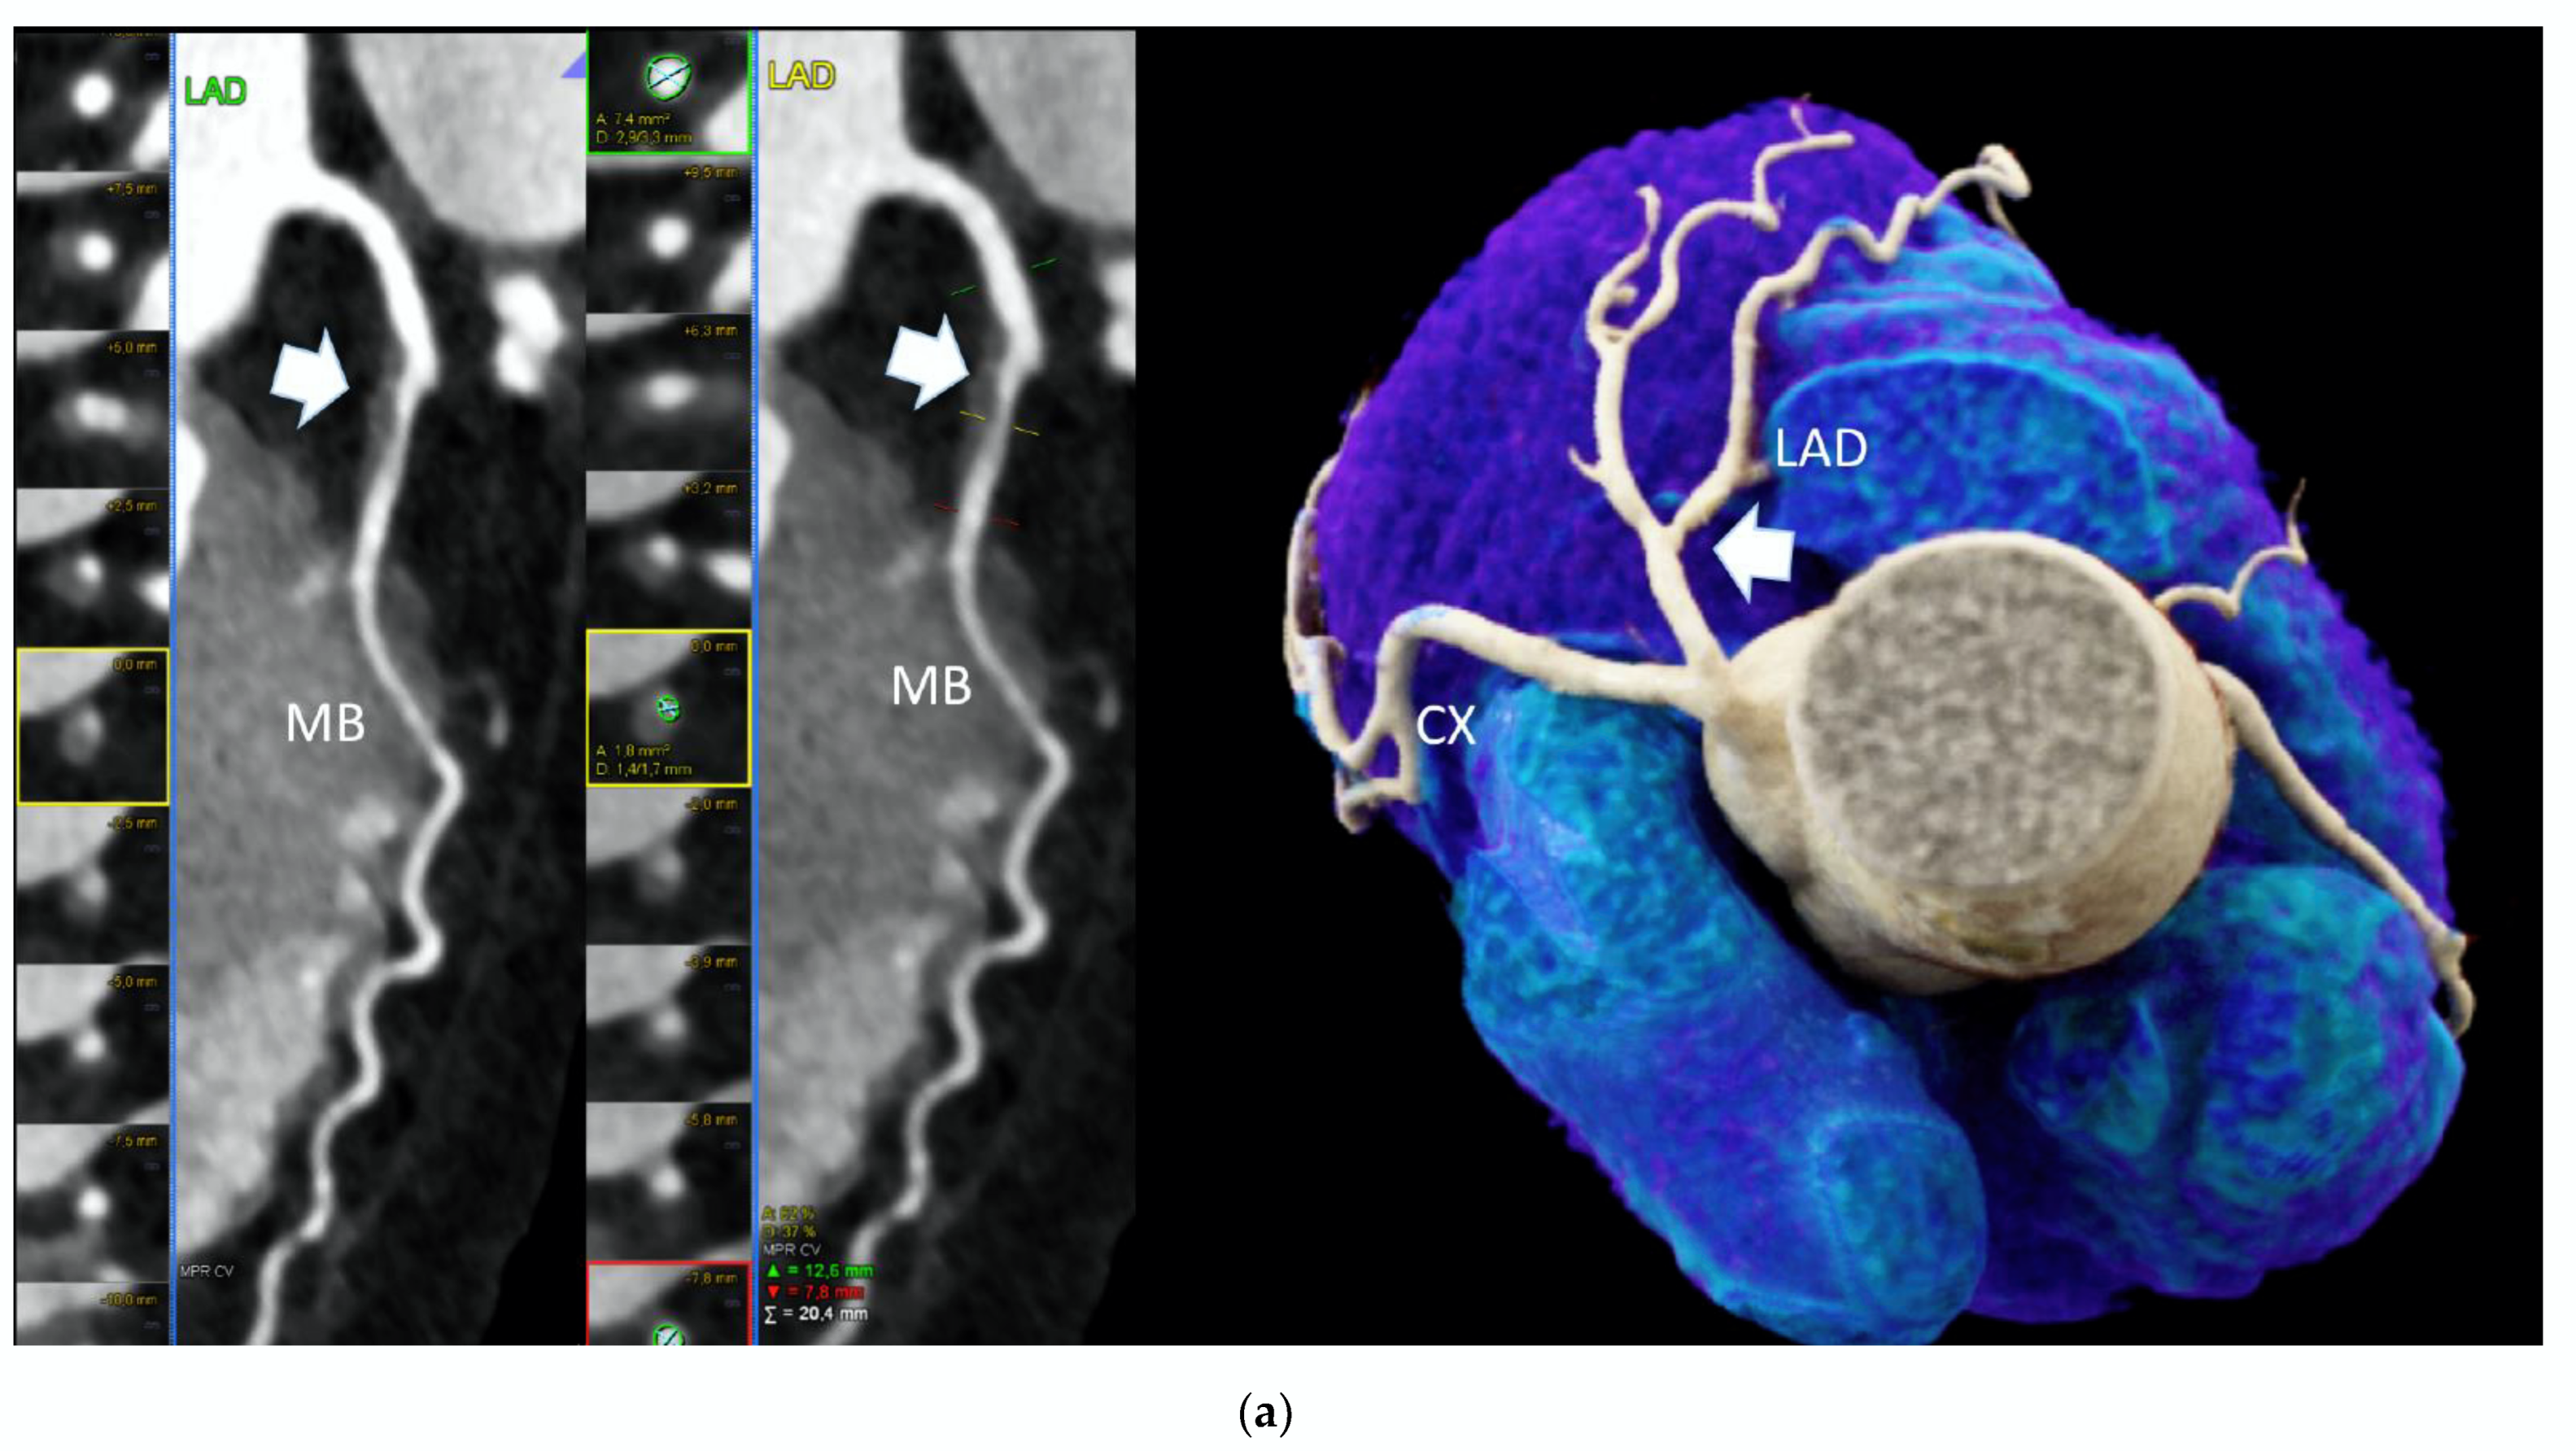

2.1. Cardiac Computed Tomography

2.1.2. Coronary CTA